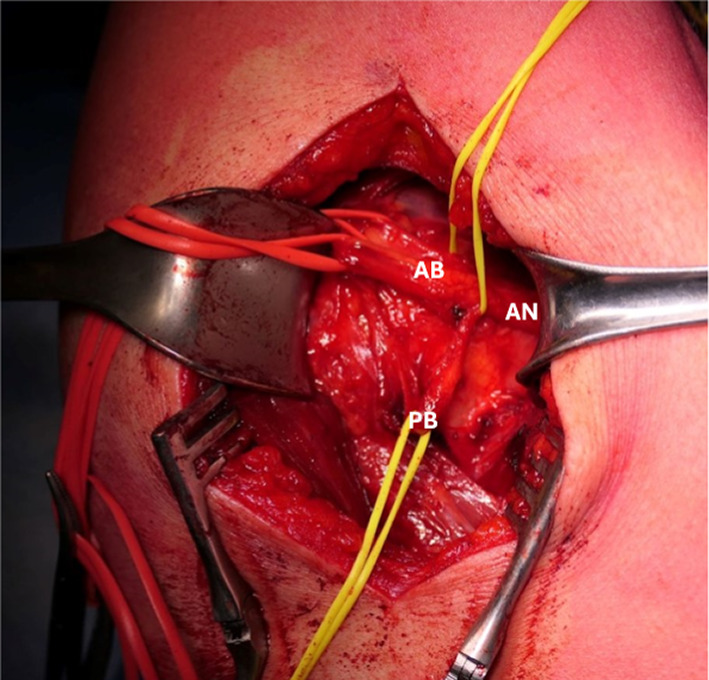

Background: Quadrilateral space syndrome is a painful disorder of the shoulder caused by static or dynamic entrapment of the axillary nerve and the posterior humeral circumflex artery. It was first described in 1983; however, it is an uncommon syndrome that initially presents with nonspecific shoulder pain or selective deltoid atrophy, and diagnosis is often delayed owing to its rarity. Young athletes of overhead sports are more commonly affected by this syndrome. Symptoms of quadrilateral space syndrome include silent deltoid atrophy, persistent posterior shoulder pain, paresthesias, and tenderness over the quadrilateral space. Vascular symptoms may involve thrombosis and embolisms of the upper limb. Instrumental tests and imaging are not always conclusive, leading to frequent misdiagnosis of the syndrome.

Patients and methods: The aim of this study is to present a case series of four patients diagnosed with neurogenic quadrilateral space syndrome, describe different clinical presentations, and suggest tips for diagnosing this syndrome. All patients underwent a detailed medical history collection, were interviewed about the sports and hobbies they engaged in, and received a comprehensive clinical examination of the neck and shoulder. Patients also underwent diagnostic exams such as magnetic resonance imaging (MRI) and electromyography. An ultrasound-guided injection of local anesthetic was performed into the quadrilateral space.